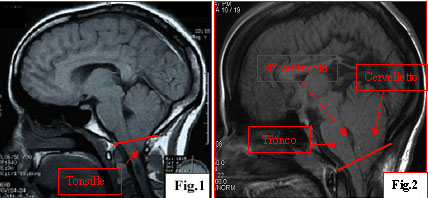

Figura 1: Esempio di malformazione di Arnold-Chiari I con siringomielia associata. Le tonsille cerebellari sono dislocate nel canale cervicale. A livello del corpo di C2 vi � una piccola dilatazione del canale centromidollare. Figura 2: Esempio di malformazione di Arnold-Chiari II con siringomielia e associato mielomeningocele. Notare la discesa in toto del cervelletto, del 4� ventricolo e tronco. Nei casi sintomatici � indicato un intervento chirurgico di decompressione suboccipitale, al fine di aumentare il volume della fossa cranica posteriore, di consentire una decompressione delle strutture encefaliche ivi contenute e il ripristino di una normale circolazione del liquor. I risultati del trattamento chirurgico sono in genere buoni quando esso viene instaurato precocemente. La riuscita chirurgica � dell�80-90%. Obiettivo del trattamento � la risoluzione dei sintomi d�esordio e, nei casi con siringomielia sintomatica associata, un arresto della progressione. |